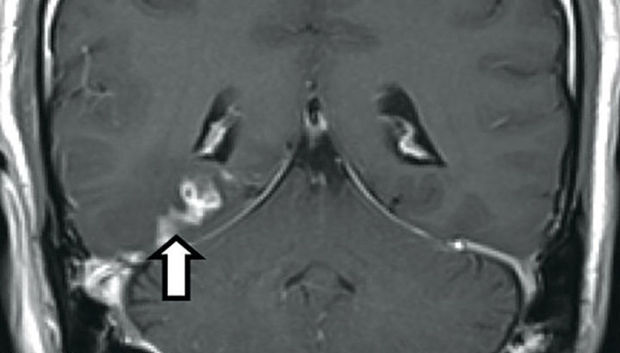

Обследование показало, что в его мозге имеется некое образование длиной около четырех сантиметров, однако тесты исключили опухоль. Дальнейшие анализы установили: в мозге мужчины находится свиной цепень.

Как вспомнил сам пациент, около десяти лет назад в Мексике он съел плохо прожаренный стейк из свинины.

Вероятно, тогда паразит и попал в организм человека. В ходе операции ленточного червя удалили из мозга мужчины, и он полностью восстановился.